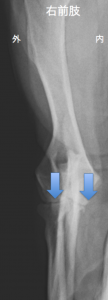

写真 4ヶ月歳の肘関節と9年後の同じ肘関節。関節は重度に変形をし、関節の動きは極端に制約され、持続的な跛行が見られてしまっていました。4ヶ月齢時、症状は見られませんでしたが、わずかですが関節の硬化症(白くなる)が認められていました。

写真 肘関節の早期診断。正常な関節との比較。関節の底部に白く変化している(骨硬化症)↓が診られます